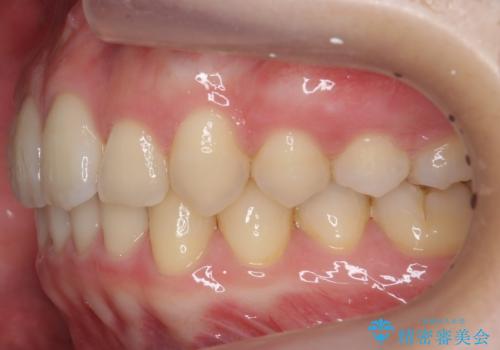

- 前歯の前突を主訴に来院。

かみ合わせが深く、また奥歯のかみ合わせも全体的に上が前にずれていました。

インビザライン矯正だけでなく、途中ワイヤー矯正もはさみました。前歯のかみ合わせが深く、本当に大変な治療でしたが協力度も高く非抜歯で上の奥歯を後ろに動かすことができました。